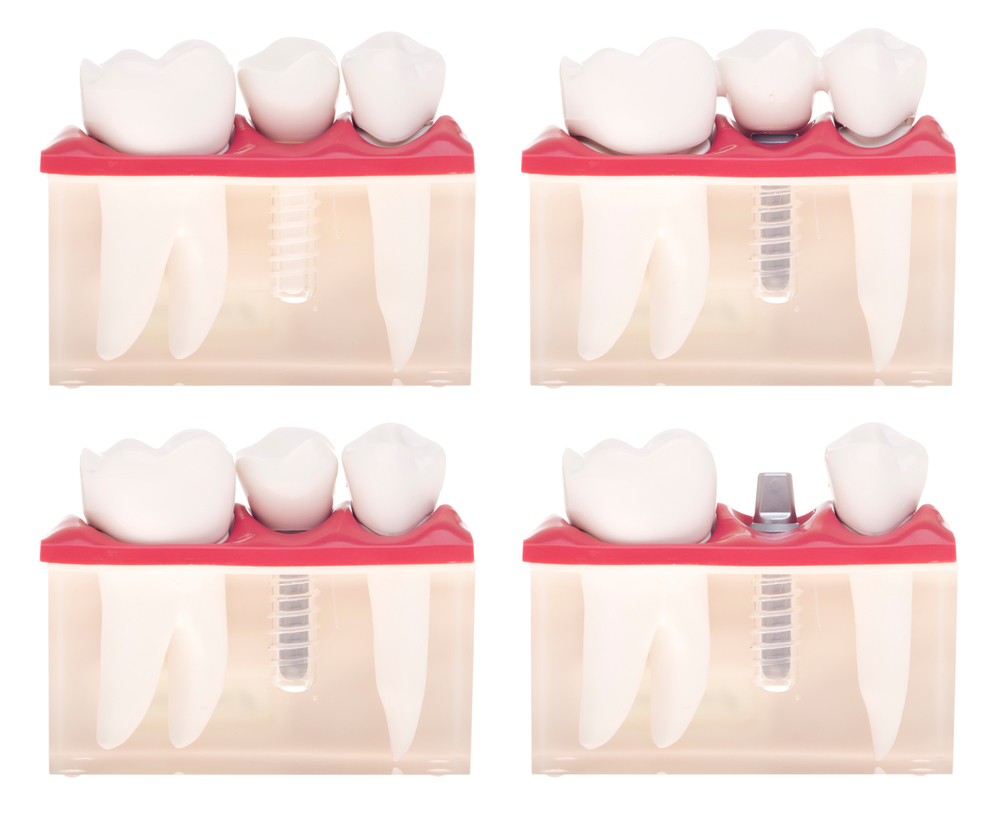

The various types of crowns and caps